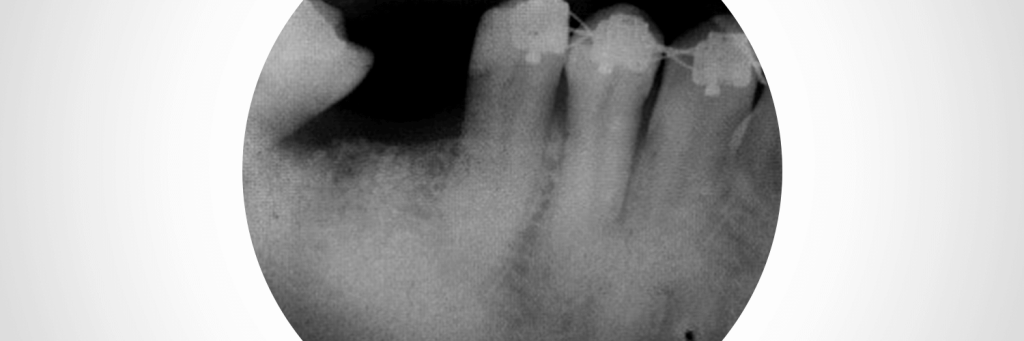

Preenchimento alveolar com enxerto ósseo sintético

Paciente, sexo masculino, 30 anos, compareceu à clínica Naturale Odontologia, cidade de Joinville, apresentando lesão endoperiodontal com envolvimento de furca associada à mobilidade no elemento 46. Optou-se pela regeneração através de biomaterial sintético à base de fosfato de cálcio no mesmo ato cirúrgico da exodontia. A escolha se deveu dada sua excelente praticidade clínica […]